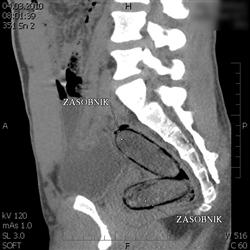

Olomoučtí celníci prováděli ve čtvrtek 4. března v nočních hodinách kontrolu mezinárodního rychlíku. Ten jel z Polska do Rakouska. Všimli si jednoho z cestujících, který vykazoval indicie naznačující pašování drogy. Pocházel z oblasti západní Afriky a trvalý pobyt měl v Evropské unii. Celníci provedli další kontroly za účelem detekce přítomnosti omamné psychotropní látky. Ty potvrdily výskyt drogy v těle. Následné CT vyšetření s jistotou prokázalo, že muž ukrývá v tělních dutinách čtyři kontejnery s neznámou látkou. Po vyloučení těchto předmětů z těla, za přítomnosti celníků, byl proveden drogový test a orientační vážení. Pasažér převážel v tělních dutinách 114 gramů kokainu. V lednu byl odhalen podobný případ, kdy cizinec přepravoval stejným způsobem 160 gramů kokainu.